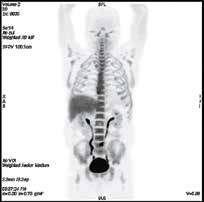

121031100301-1. «Прогнозирование эффективности специфической терапии с помощью позитронной эмиссионной томографии с 3′-дезокси-3′-[18F]фтор-л-тимидин при миелоидных новообразованиях». Выявлено, что степень захвата 18F-ФЛТ коррелирует с объемом опухолевой массы и пролиферативной активностью злокачественных гемопоэтических клеток. Так, при острых миелоидных лейкозах (ОМЛ) активный захват 18F-ФЛТ в костном мозге был выявлен в дебюте болезни, при его рецидиве или рефрактерном течении. Все параметры ПЭТ-КТ 18F-ФЛТ были сопоставлены с показателями захвата тимидина у пациента без онкологической патологии. При хронических миелоидных новообразованиях активность тимидина в костном мозге была существенно выше у пациентов с трансформацией в бластный криз. У последних этот показатель был сравним с уровнем захвата тимидина у пациентов с ОМЛ. На данном этапе продолжается анализ показателей для выявления роли исследования в оценке пролиферативной активности печени и селезенки при хронических миелоидных новообразованиях.

| ПЭТ-КТ с 18F-ФЛТ в норме с физиологическим накоплением РФП в печени и КМ | |